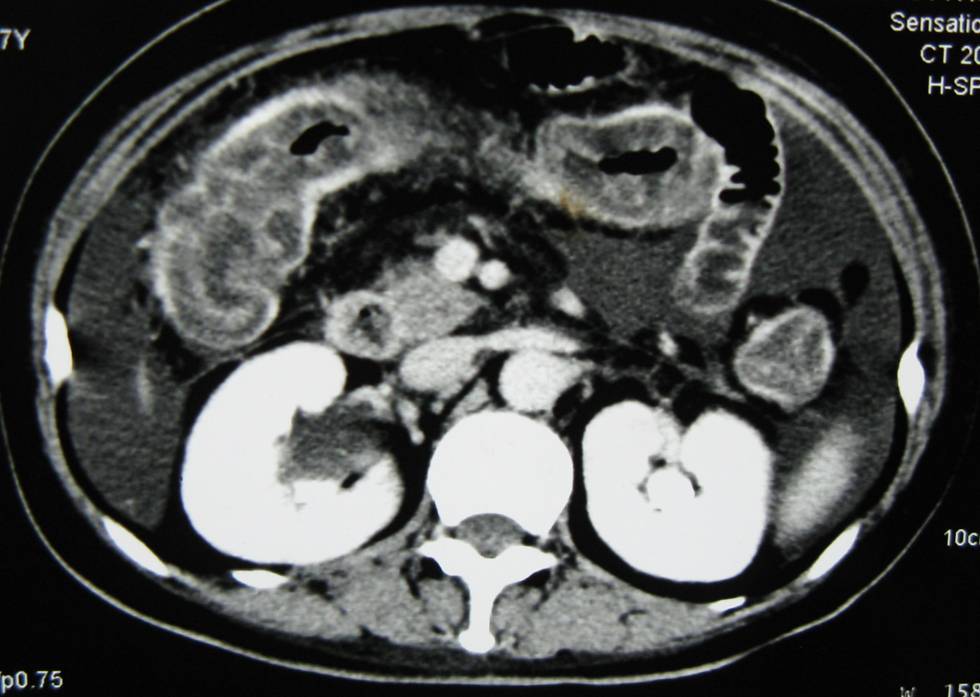

患者3月半前无明显诱因出现恶心、呕吐4次,量较多,呕吐物为胃内容物及胆汁,无呕血及呕隔夜宿食,非喷射性,伴上腹阵发绞痛,无放射,伴腹胀,呕吐后可稍缓解。无发热、腹痛、腹泻、黑便,有排气排便,就诊于当地医院,查腹部B超示“左侧上腹肠管壁增厚,炎症可能性大,腹盆腔中等量积液”,胃镜示“胆汁返流性胃炎、糜烂性胃炎”,结肠镜示“直-乙状结肠炎”,予抗炎、对症治疗,症状减轻后出院。3个月前无明显诱因症状再发加重,表现同前,伴腹泻,为棕色稀便,1-2次/天,每次量少,约30ml,偶带脓,未见血,伴里急后重,伴腹围增大、尿量减少及双下肢水肿,伴发热(体温不详)、盗汗、乏力、双膝双踝关节疼痛、脱发,无皮疹、光过敏、口腔溃疡、口干、眼干,体温于抗感染治疗1周后恢复正常。查腹部CT示“结肠壁普遍明显增厚,胸水、腹水较前增加”,腹部立位平片示“肠梗阻”,行多次腹水检查结果提示渗出液,单个核细胞为主,ADA轻度升高,血常规示全血细胞减少,尿蛋白2+,ANA1:100,考虑“腹痛、腹水、肠梗阻原因待查 肠结核、结核性腹膜炎?系统性红斑狼疮?”予禁食水、胃肠减压、石蜡油通便后,腹痛及呕吐有所缓解,腹泻增加至约7-10次/天,为橙色稀水便。25天前加用试验性抗痨治疗及强的松+羟氯喹治疗,1周前腹痛消失,仍有呕吐及腹泻,现为进一步诊治收入院。患者自发病以来饮食、睡眠差,大便如前述,小便少,体重下降20公斤。